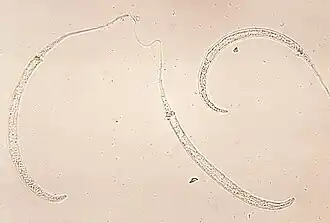

Larves de Dracunculus medinensis.

Les Camallanida sont un ordre de nématodes (les nématodes sont un embranchement de vers non segmentés, recouverts d'une épaisse cuticule et mènant une vie libre ou parasitaire). Selon l'IRMNG (23 mai 2021)[1], Camallanida est synonyme de Spirurida.